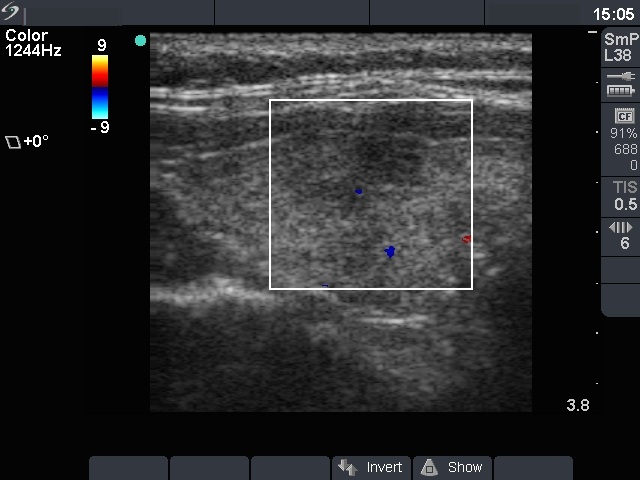

Hashimoto thyroiditis - Case 61

Right lobe, color mode

Compare the two series of pictures. Hashimoto's thyroiditis frequently has a similar appearance as observed in the case of de Quervain's thyroiditis. The patchy appearance i.e. hypoechogenic areas within an echonormal background is observed in around 70% of the former, while in more than 90% of the latter disease. In contrast with subacute thyroiditis, the hypoechogenic areas in most of the Hashimoto's cases have irregular but sharp borders. In the cases demonstrated above, the only difference between the ultrasound appearance is the pattern of the hypoechogenic areas. These foci are more blurred in the case of subacute thyroiditis. Nevertheless, the sonographic pattern itself is not diagnostic.